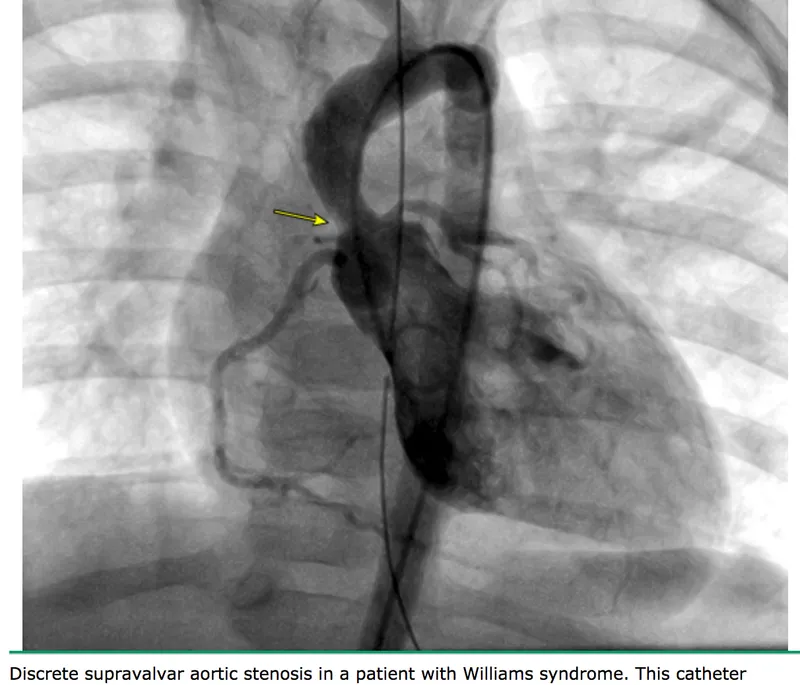

Left ventricular pressure overload (aortic stenosis, hypertension) produces concentric hypertrophy-wall thickness increases from 9-11 mm to >15 mm while cavity size remains normal. The hypertrophied ventricle generates gradients >50 mmHg in severe AS, maintaining forward flow until decompensation.

💡 Master This: Afterload equals wall stress during ejection, calculated by LaPlace's Law: Wall Stress = (P × r) / (2 × h), where P = pressure, r = radius, h = wall thickness. Aortic stenosis increases pressure afterload; LV hypertrophy compensates by increasing thickness, normalizing wall stress until severe stenosis (gradient >50 mmHg) overwhelms compensation.